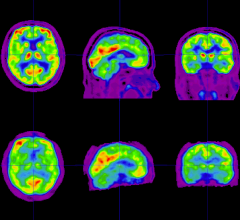

Positron emission tomography (PET) is a nuclear imaging technology (also referred to as molecular imaging) that enables visualization of metabolic processes in the body. The basics of PET imaging is that the technique detects pairs of gamma rays emitted indirectly by a positron-emitting radionuclide (also called radiopharmaceuticals, radionuclides or radiotracer). The tracer is injected into a vein on a biologically active molecule, usually a sugar that is used for cellular energy. PET systems have sensitive detector panels to capture gamma ray emissions from inside the body and use software to plot to triangulate the source of the emissions, creating 3-D computed tomography images of the tracer concentrations within the body.